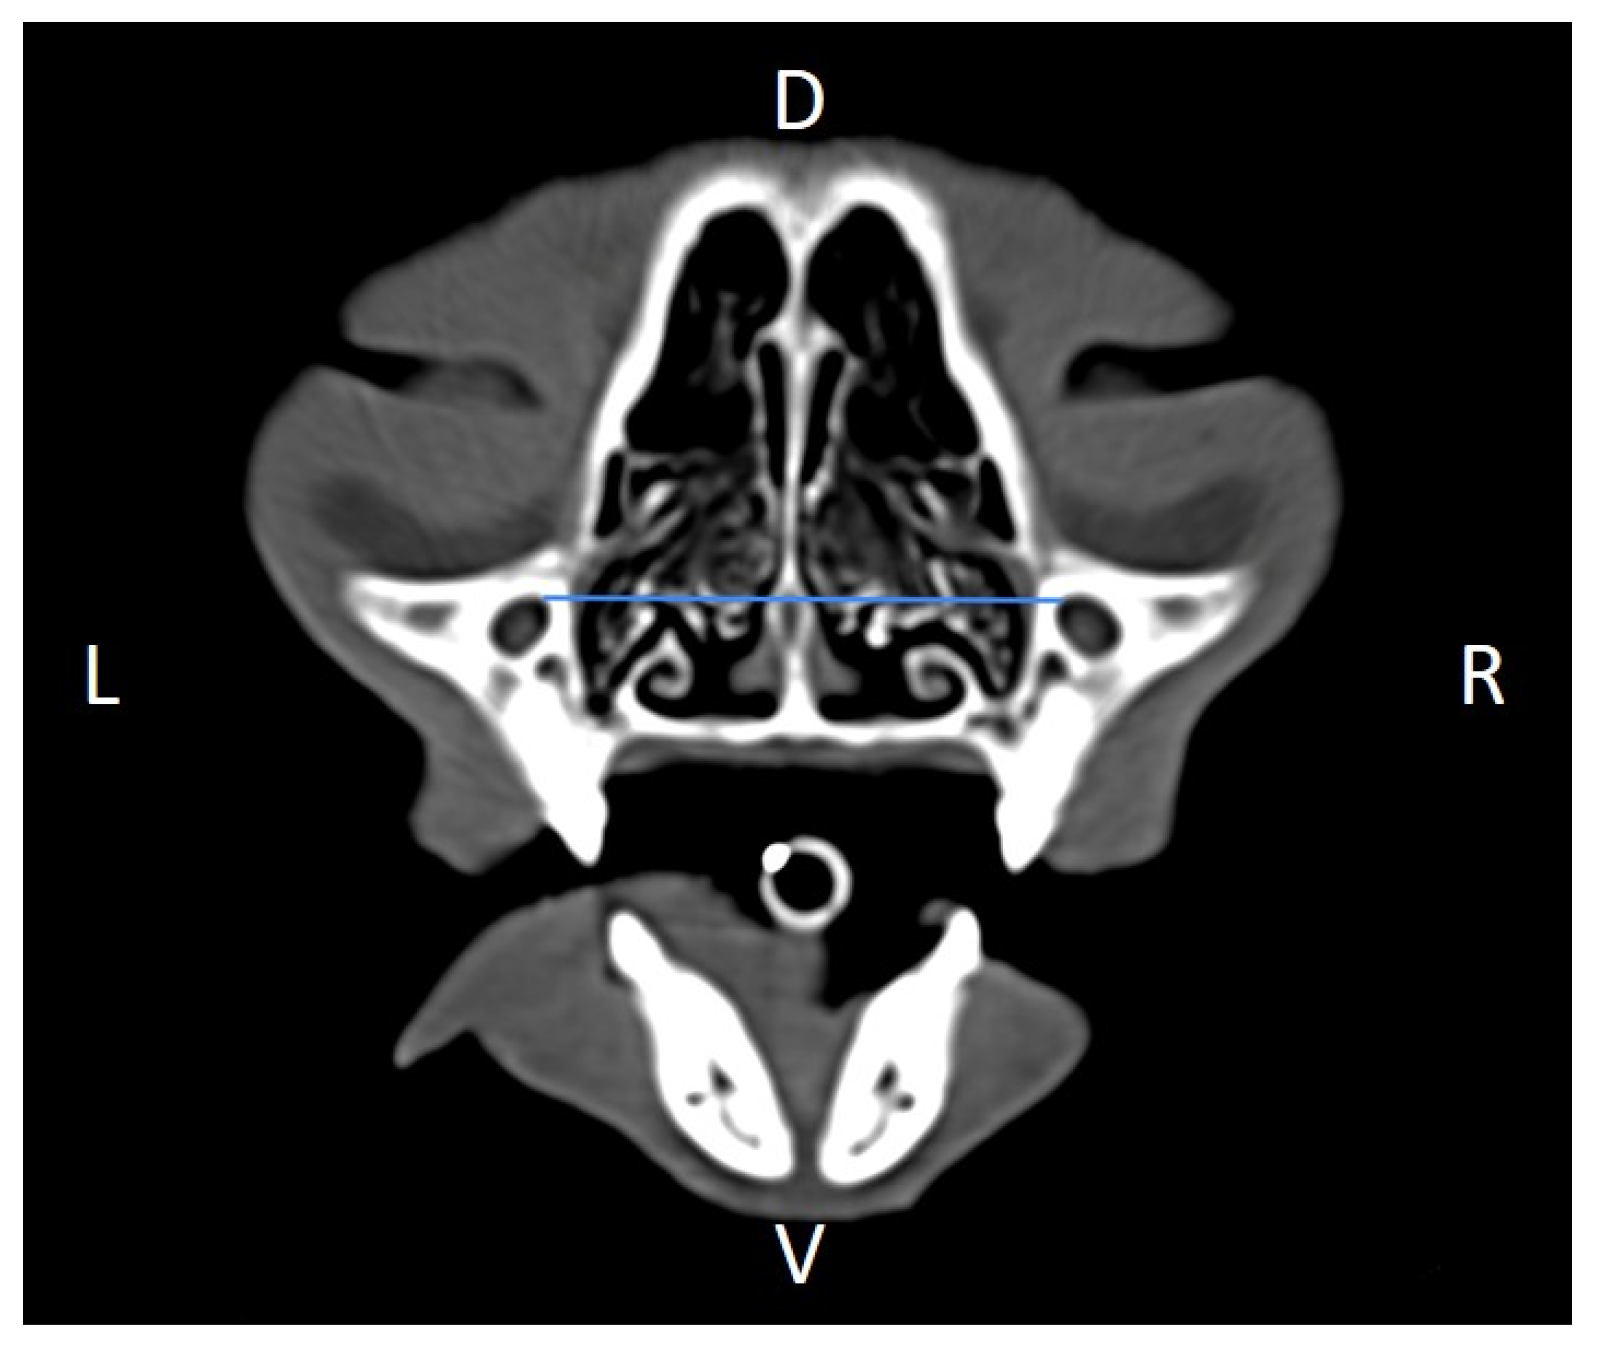

Linear morphometric parameters (Table 1) were obtained directly from CT images using HorosTM v3.3.6.dmg DICOM software with bone filters. Prior to measurement, all images were calibrated from pixels to millimeters. A preliminary study and prior training were conducted, to establish anatomical landmarks that would allow for the repeatability of the measurement methodology by J.F.R., A.R.S., S.A.-P. Recorded variables included infraorbital foramen major axis (Figure 2), minor axis (Figure 3) and length (Figure 4), distance between infraorbital foramina (DIF) (Figure 5), orbital height and width (Figure 6 and Figure 7), zygomatic arch width (Figure 8), skull width and length (Figure 9). Ratios were calculated to normalize for skull size. As preliminary results revealed adequate repeatability of measurements, and in order to reduce the analysis margin of error, two measurements of each studied parameter were performed. The measurements were performed by the same operator (to reduce interpersonal errors), and each measurement of each parameter was performed at different times, in order to reduce intrapersonal errors. Then, the arithmetic mean of the measurements was calculated.

Figure 5. Distance between infraorbital foramina (DIF) measured on a transverse CT image (blue line). D, dorsal, L, left, R, right, V, ventral.